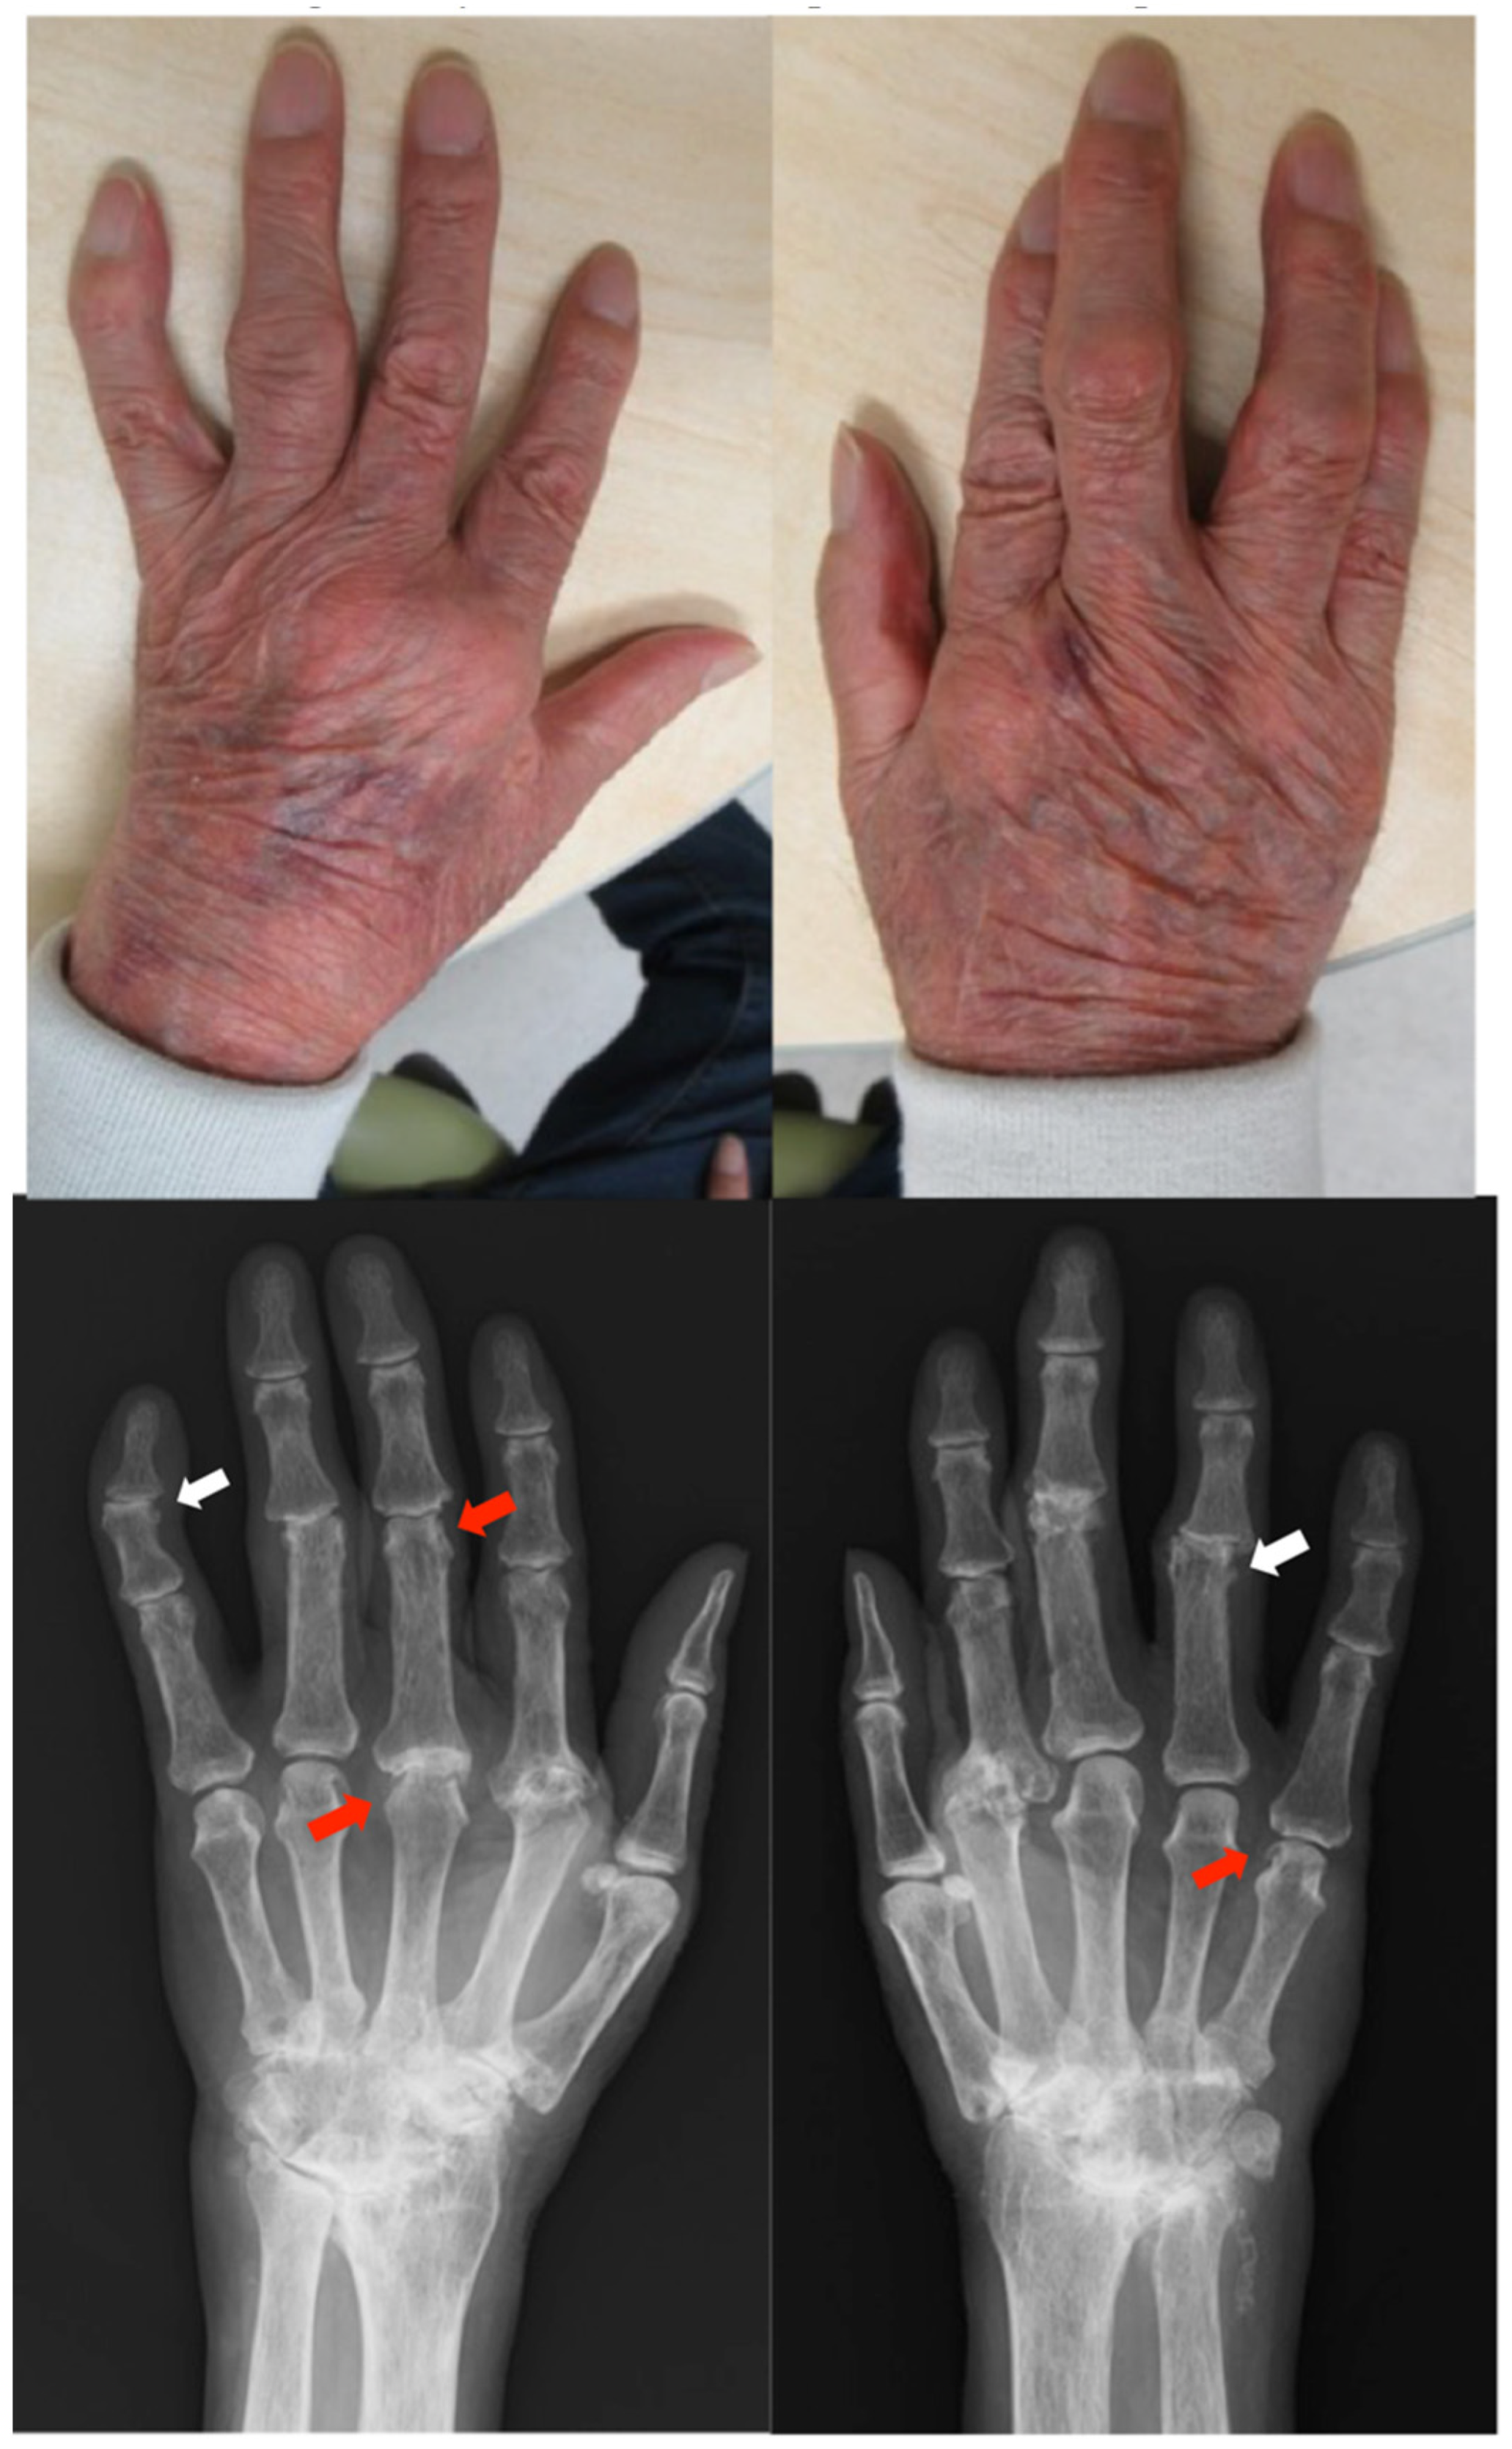

Clinical findings: The patient had red plaques covered by white scales on the head, trunk, and extremities (PASI score: 17.8) and pain and tenderness in his wrist joints. Radiographs showed symmetrical subluxation of the second metacarpophalangeal (MCP) joint and numerous bone erosions in the bare area (where the synovium is in direct contact with the bone) at the peripheral interphalangeal (PIP) and MCP joints. Severe narrowing of the joint space was observed in the carpal bones. The left distal interphalangeal (DIP) and right PIP joints showed bone proliferation, suggesting PsA (Figure 1). The patient was diagnosed with RA and PsA.

Figure 1.

Clinical photographs and radiographs of the hands in case 1. The finger joints are swollen and deformed. Radiographs show symmetrical subluxation of the second MCP joints and bone erosions at the PIP and MCP joints (red arrow). Severe osteolysis and destruction occur on multiple joint surfaces. Severe joint space narrowing and tonic change are depicted in both carpal bones. The left DIP and right PIP joints show bone proliferation suspicious for PsA (white arrow). MCP, metacarpophalangeal; PIP, peripheral interphalangeal; DIP, distal interphalangeal.